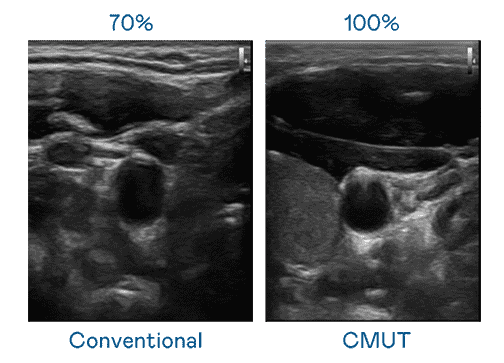

CMUT 技术是一种用电容式微机电元件来产生超音波讯号的技术。。。与传统 PZT 压电式技术相比,,,CMUT 频宽增加 30%,,,更宽频的超音波讯号让影像解析度大幅提升,,,,是实现高影像品质医疗超音波扫描、、、促进精准医疗发展的关键技术。。

大频宽带来超清晰影像

超音波影像的解析度高低,,,,首先取决于探头能发出的讯号频宽。。。。尊龙z6 CMUT 可提供高清晰的超音波讯号,,,,提供高频宽、、、、高灵敏度、、、、影像纹理细节更高的超音波影像,,,,协助医护人员缩短影像判读时间及利用精准的医疗影像进行诊断。。。